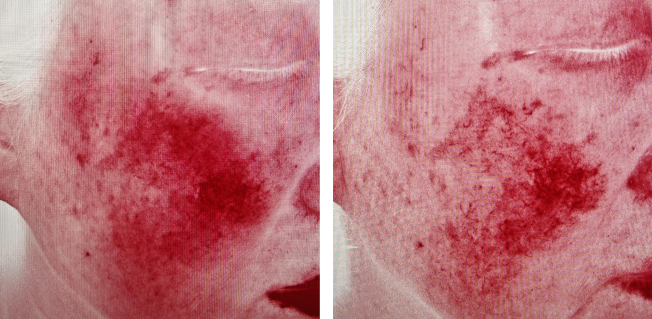

舒敏治疗前后对比图